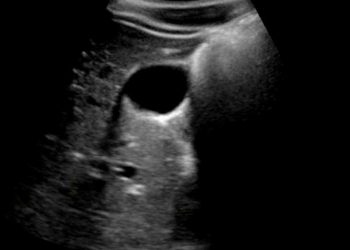

Yan Gölgelenme Artefaktı, ultrasonografide safra ve idrar torbası gibi içi sıvı dolu yapıların yan taraflarında görülen ve aşağıya doğru uzayabilen...